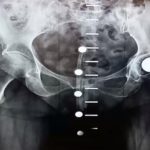

Shareable Image—-